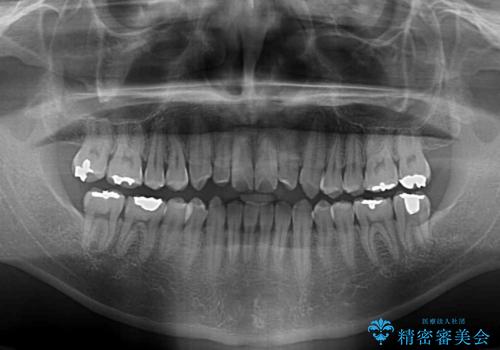

- 前歯のデコボコとクロスバイトを治したいとのことで来院された患者様です。

上下顎ともに歯列全体の側方拡大とIPR(歯と歯の間を削る)によってデコボコとクロスバイトが解消するように設計し、インビザラインにより治療を行うこととしました。

前歯の咬み合わせの調整などを行い、安定した咬み合わせに仕上げることができました。